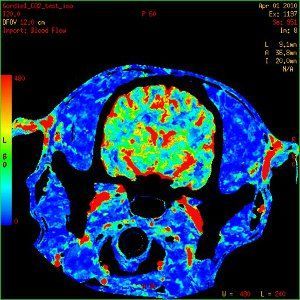

- Dynamic contrast perfusion to assess blood brain barrier permeability and regional cerebral blood flow using either MRI or CT

Dynamic perfusion CT images of a dog brain with cerebral blood flow (CBF) maps demonstrating an increase in CBF when end tidal CO2 is increased from 35mmHg (A) to 68mm Hg(B).